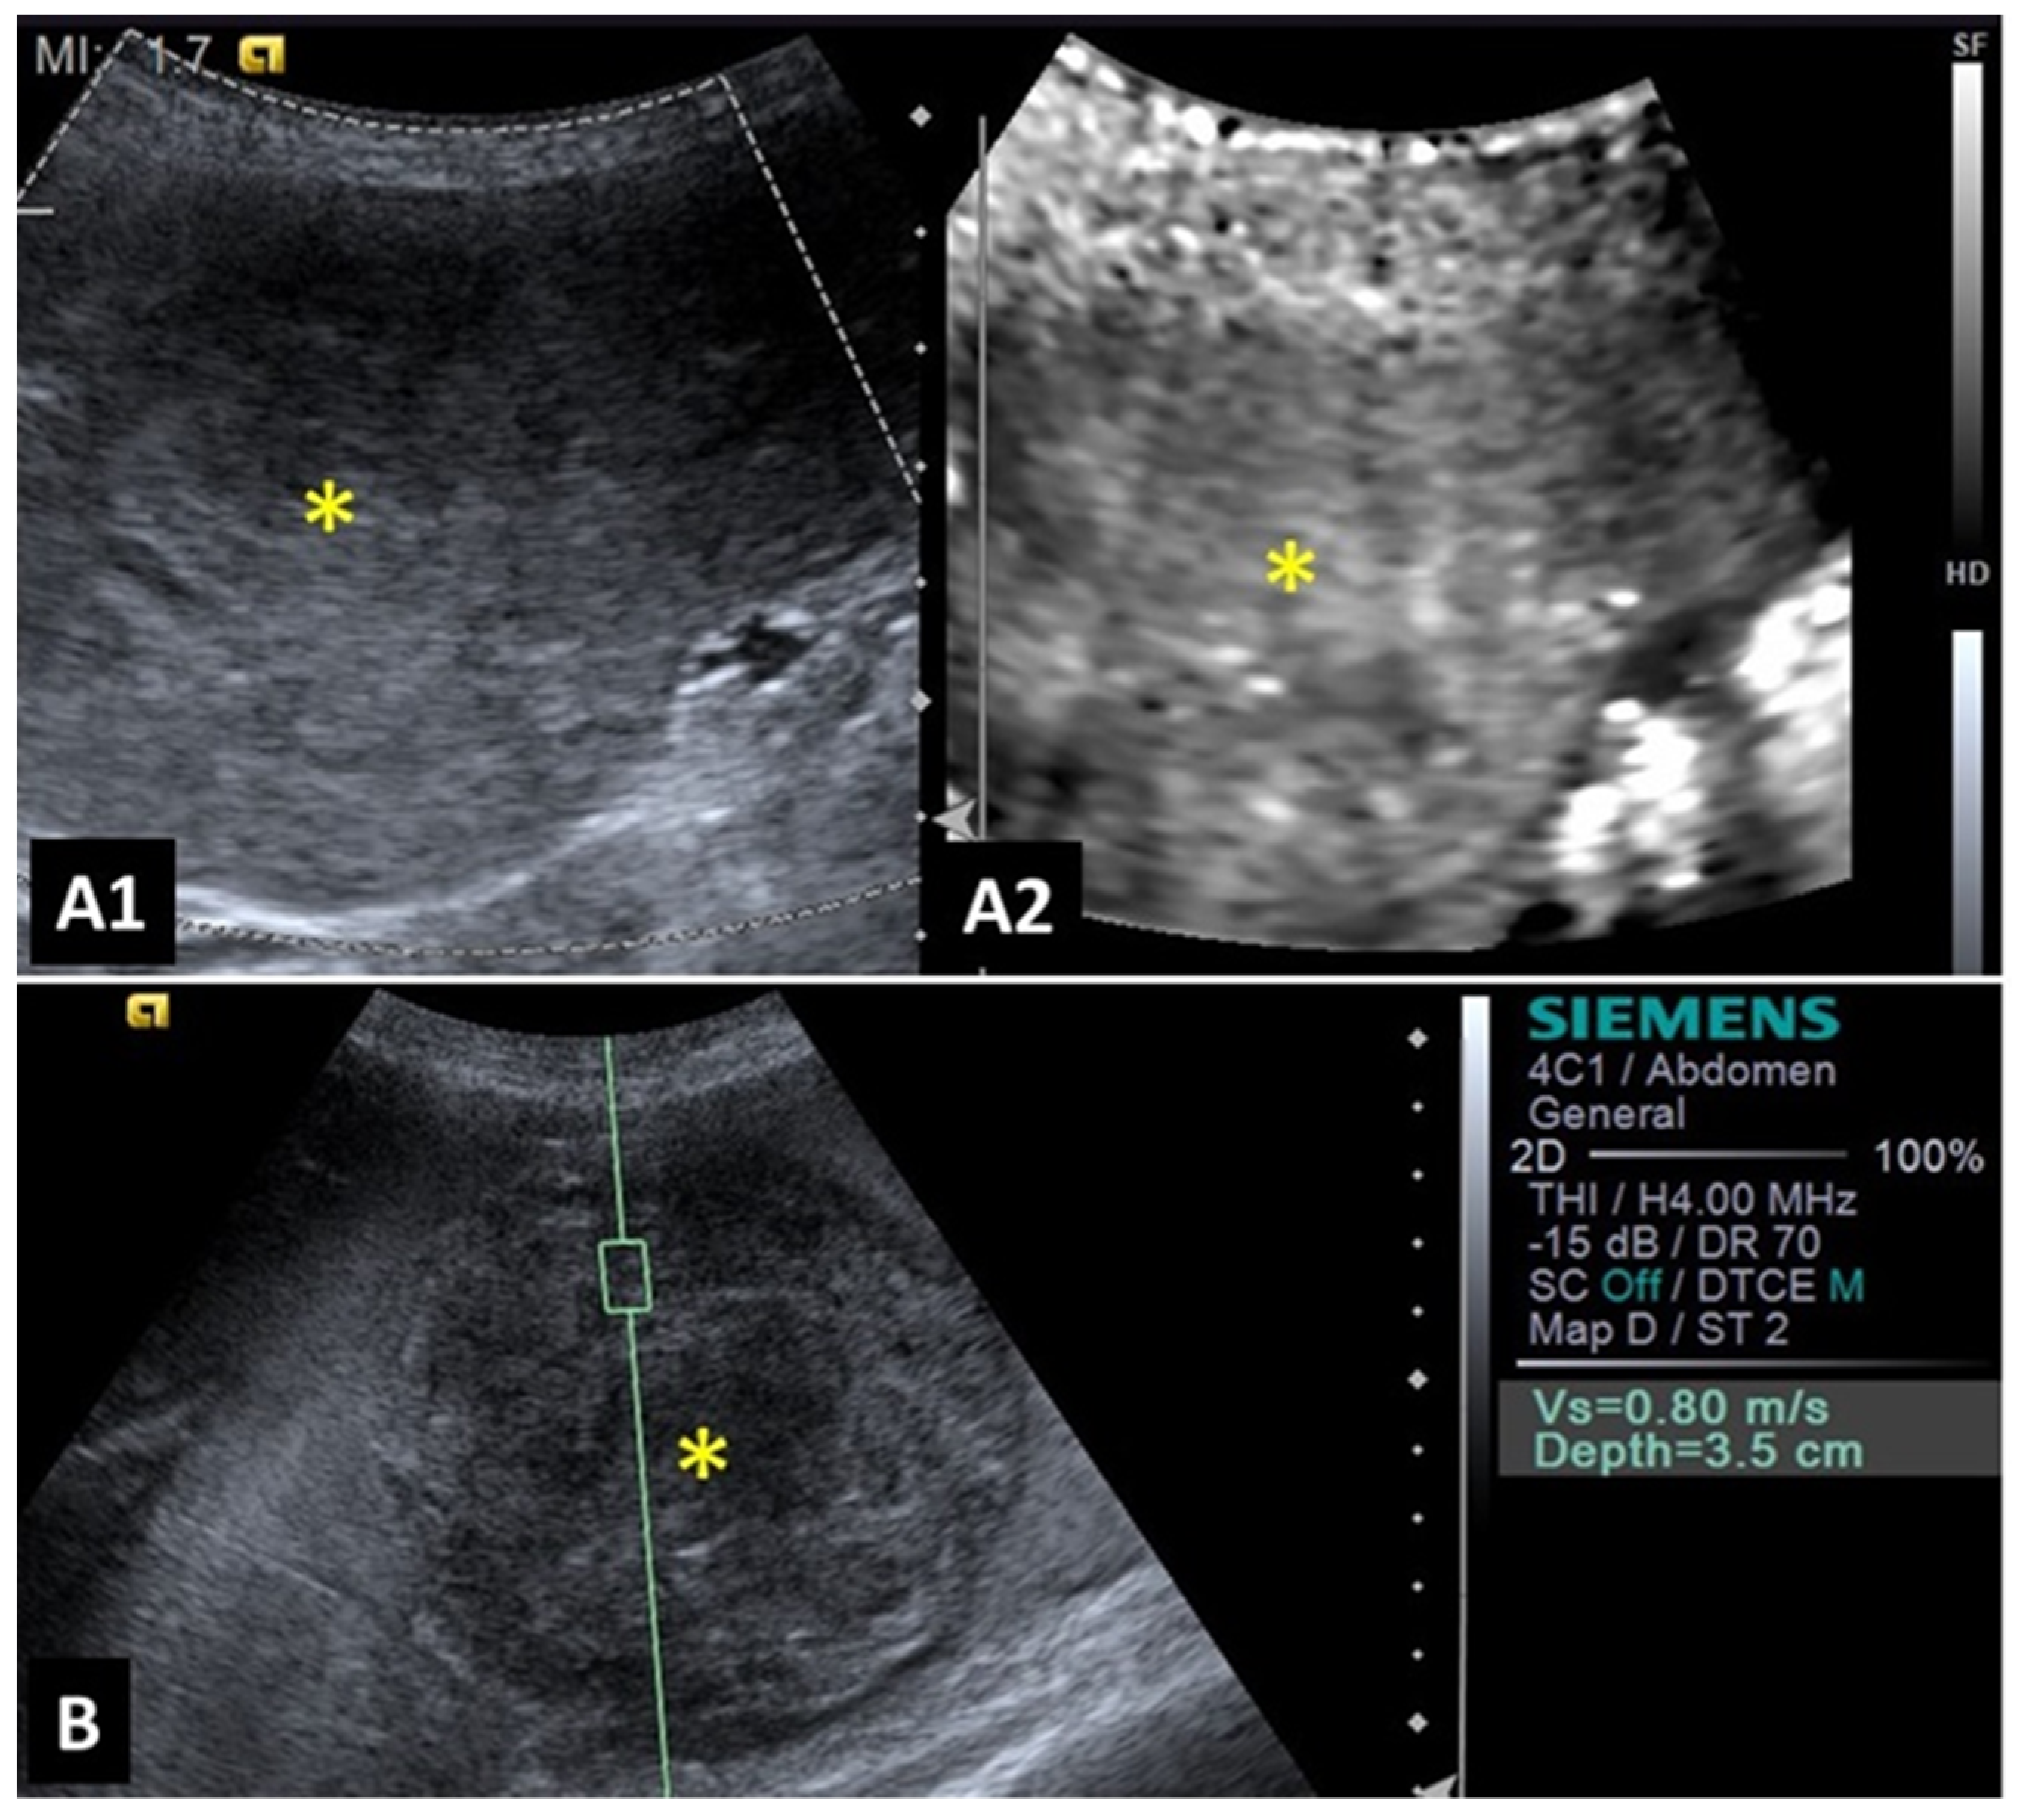

2.3. Spleen